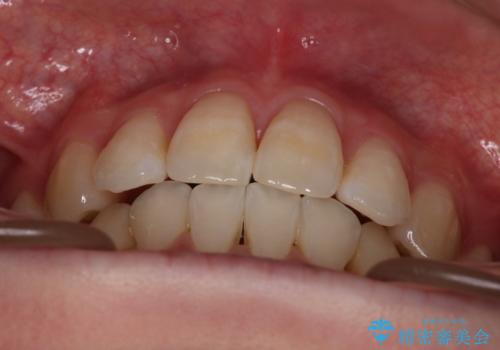

- 出っぱによる口元の閉じにくさを主訴に来院されました。上顎の出っ歯と上下顎叢生も認められたため、上下顎両側4番抜歯を行い、ワイヤー矯正で治療する治療計画を立てました。

上顎にはMI(マイクロインプラント)を埋入して固定源とすることで出っ歯の改善を図りました。

少しスペースクローズに時間がかかりましたが、MIを用いたワイヤー矯正で

主訴である出っ歯と叢生が改善されました。口も閉じやすくなり、スッキリとした口元になりました。